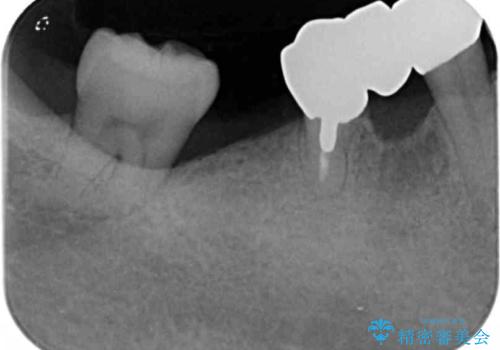

- 銀歯だらけの口腔内で将来歯がなくなるのではないかと不安になり、精査、治療を求めて来院されました。

歯周病や虫歯・強度の問題がありながらも無理やり残していた長期的な予後の見込めない歯を抜去し、インプラントを用いてしっかりと噛めるような口腔内環境の確立を目指します。